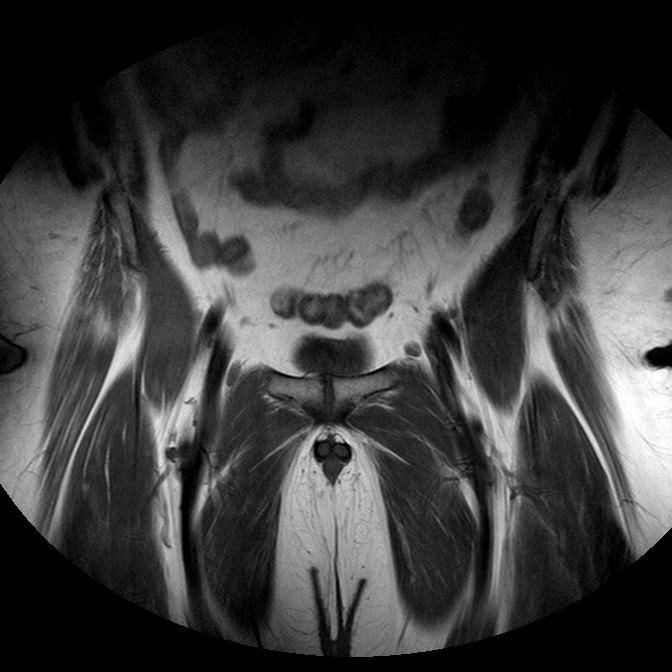

Esami: RMN BACINO

T1w TSE

Evidenti e simmetriche alterazioni osteofitosiche in regione coxo femorale con riduzione delle rime articolari. Degenerazione completa del cercine glenoideo. Non attuali segni di versamento articolare. Non segni di edema osseo che escludono attuale algodistrofia od osteonecrosi. Lieve e simmetrica riduzione del trofismo della muscolatura glutea.